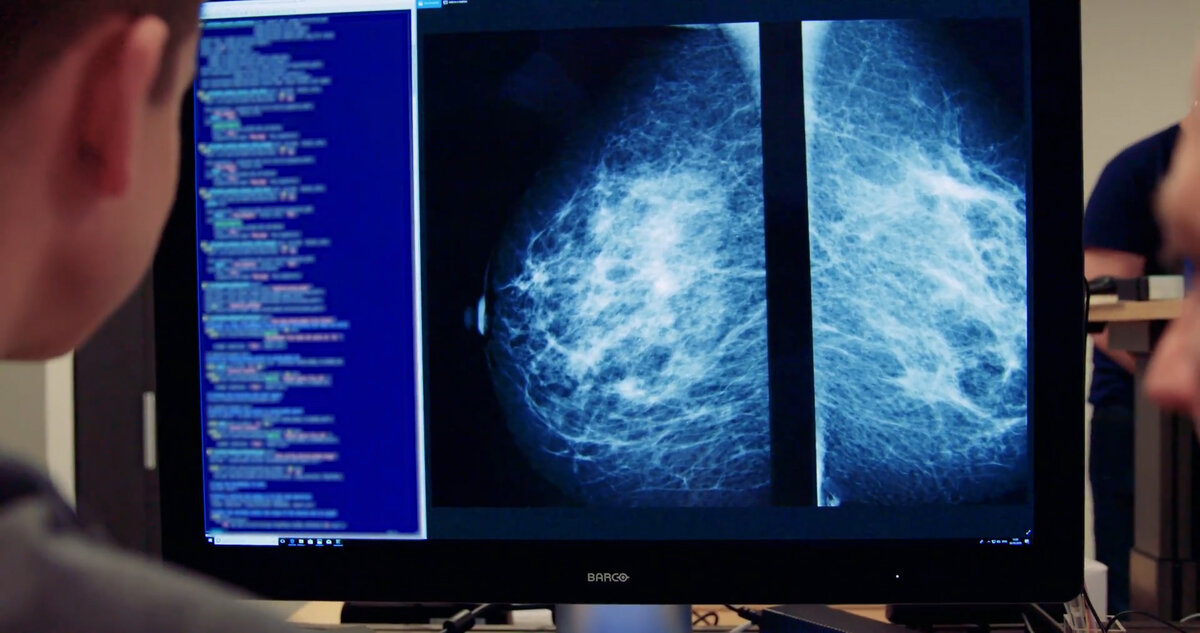

На создание и обучение Mia, которая работает на облачных вычислениях Microsoft, ушло шесть лет, и она обучалась на миллионах маммограмм, полученных от женщин со всего мира.

Mia не идеальна. У нее пока нет доступа к истории болезни пациента, поэтому, например, она может отметить кисты, которые уже были выявлены при предыдущем сканировании и признаны безвредными.

Кроме того, в соответствии с действующими нормами здравоохранения, элемент машинного обучения в ИИ-системе был отключен, поэтому он не мог обучаться в процессе работы и развиваться во время использования. При каждом обновлении он должен был проходить новую проверку.